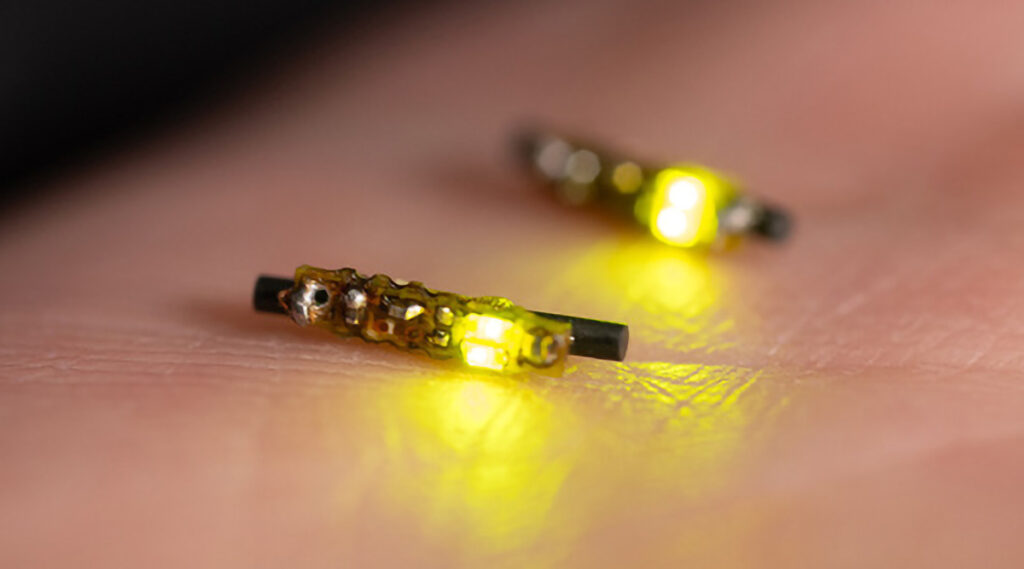

מחקר הציג טיפול חדש לפטרת ציפורניים, Trichophyton rubrum, באמצעות סילון פלזמה נייד פועם אוויר קר. הטכנולוגיה משתמשת בגלי הלם כדי להשמיד את הפטרייה ביעילות, תוך השגת שיעור הכחדה של 90% עם פרוטוקולי טיפול ספציפיים, המסמן התקדמות משמעותית בטכנולוגיות הטיפול בפטריות. חוקרים פיתחו א פְּלַסמָה מכשיר סילון הורג ביעילות 90% מפטריית ...